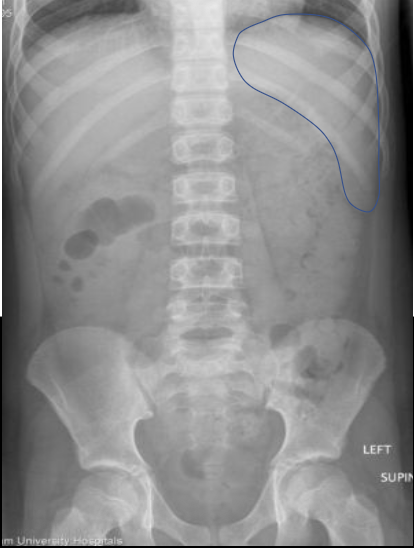

What anatomy is outlined in this image?

Spleen